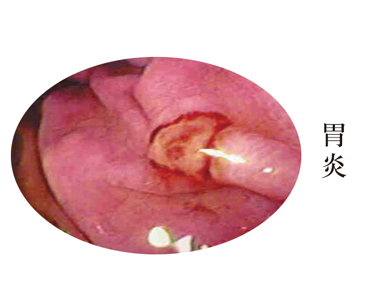

����θ����ָθ�Ĥ��������֢�Ի�ή���Բ��䡣����һ�ֳ��������ɷ�Ϊ���Ժ������������͡�����θ�׳�����Ϊ�����Ժ����������֡� ǰ�߱���Ϊ�ϸ����ʡ���ʹ����ʳ�����ĺ�Ż�£�����������������ѪΪ��Ҫ���֣���ŻѪ�ͺڷࡣ��θ������Ҫע����Щ���棿